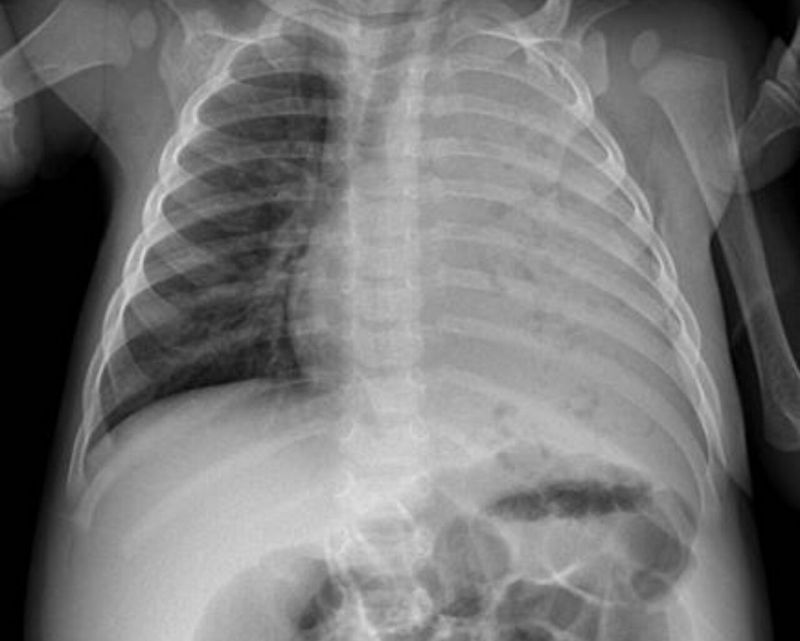

Cavitating pneumonia The chest xray shows complete opacification of the left hemithorax with numerous small lucencies throughout. Findings consistent with cavitating bacterial pneumonia